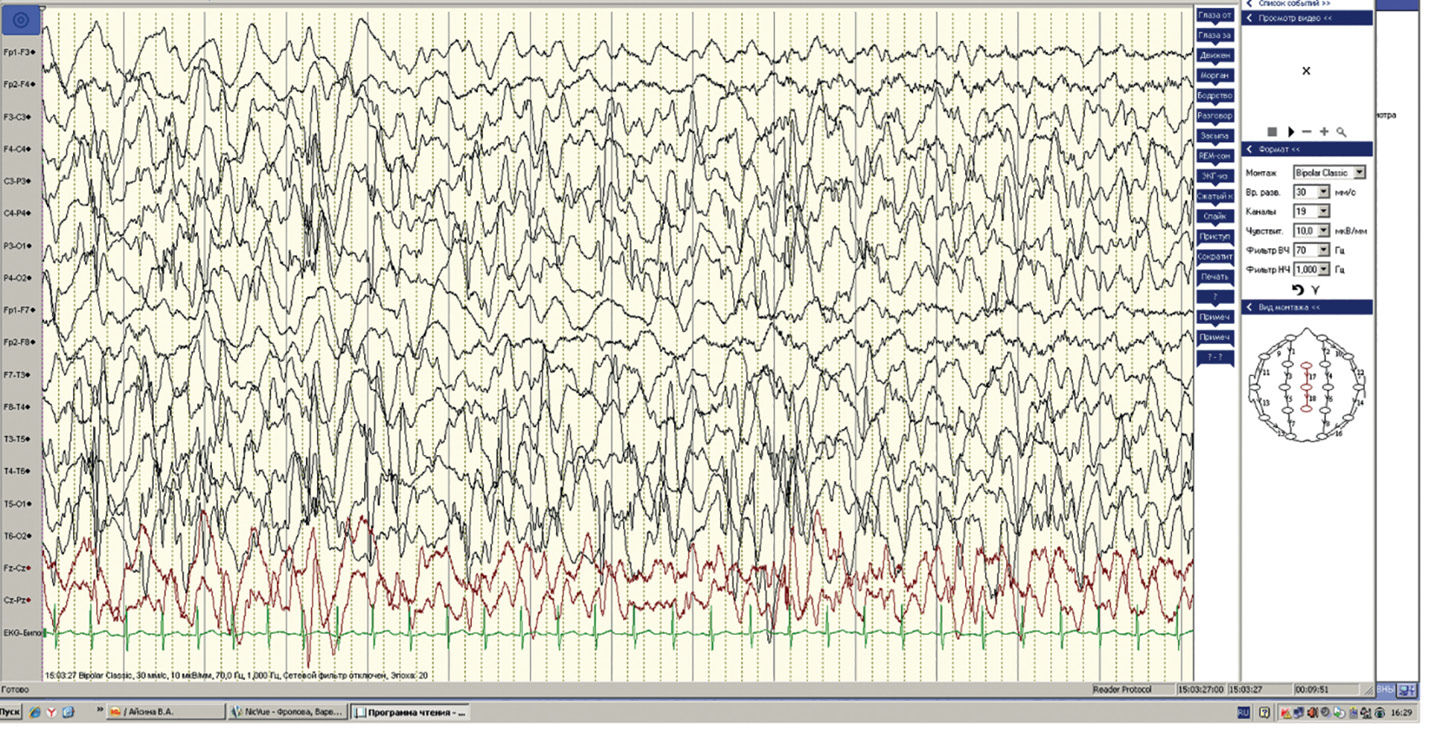

Как правило, классическая (типичная) гипсаритмия занимает 100% записи ЭЭГ. Классическую гипсаритмию можно описать как генерализованную патологическую активность, без регионального акцента и латерализации (рис. 1).

Рис. 1. Классическая гипсаритмия у ребенка 8 мес.